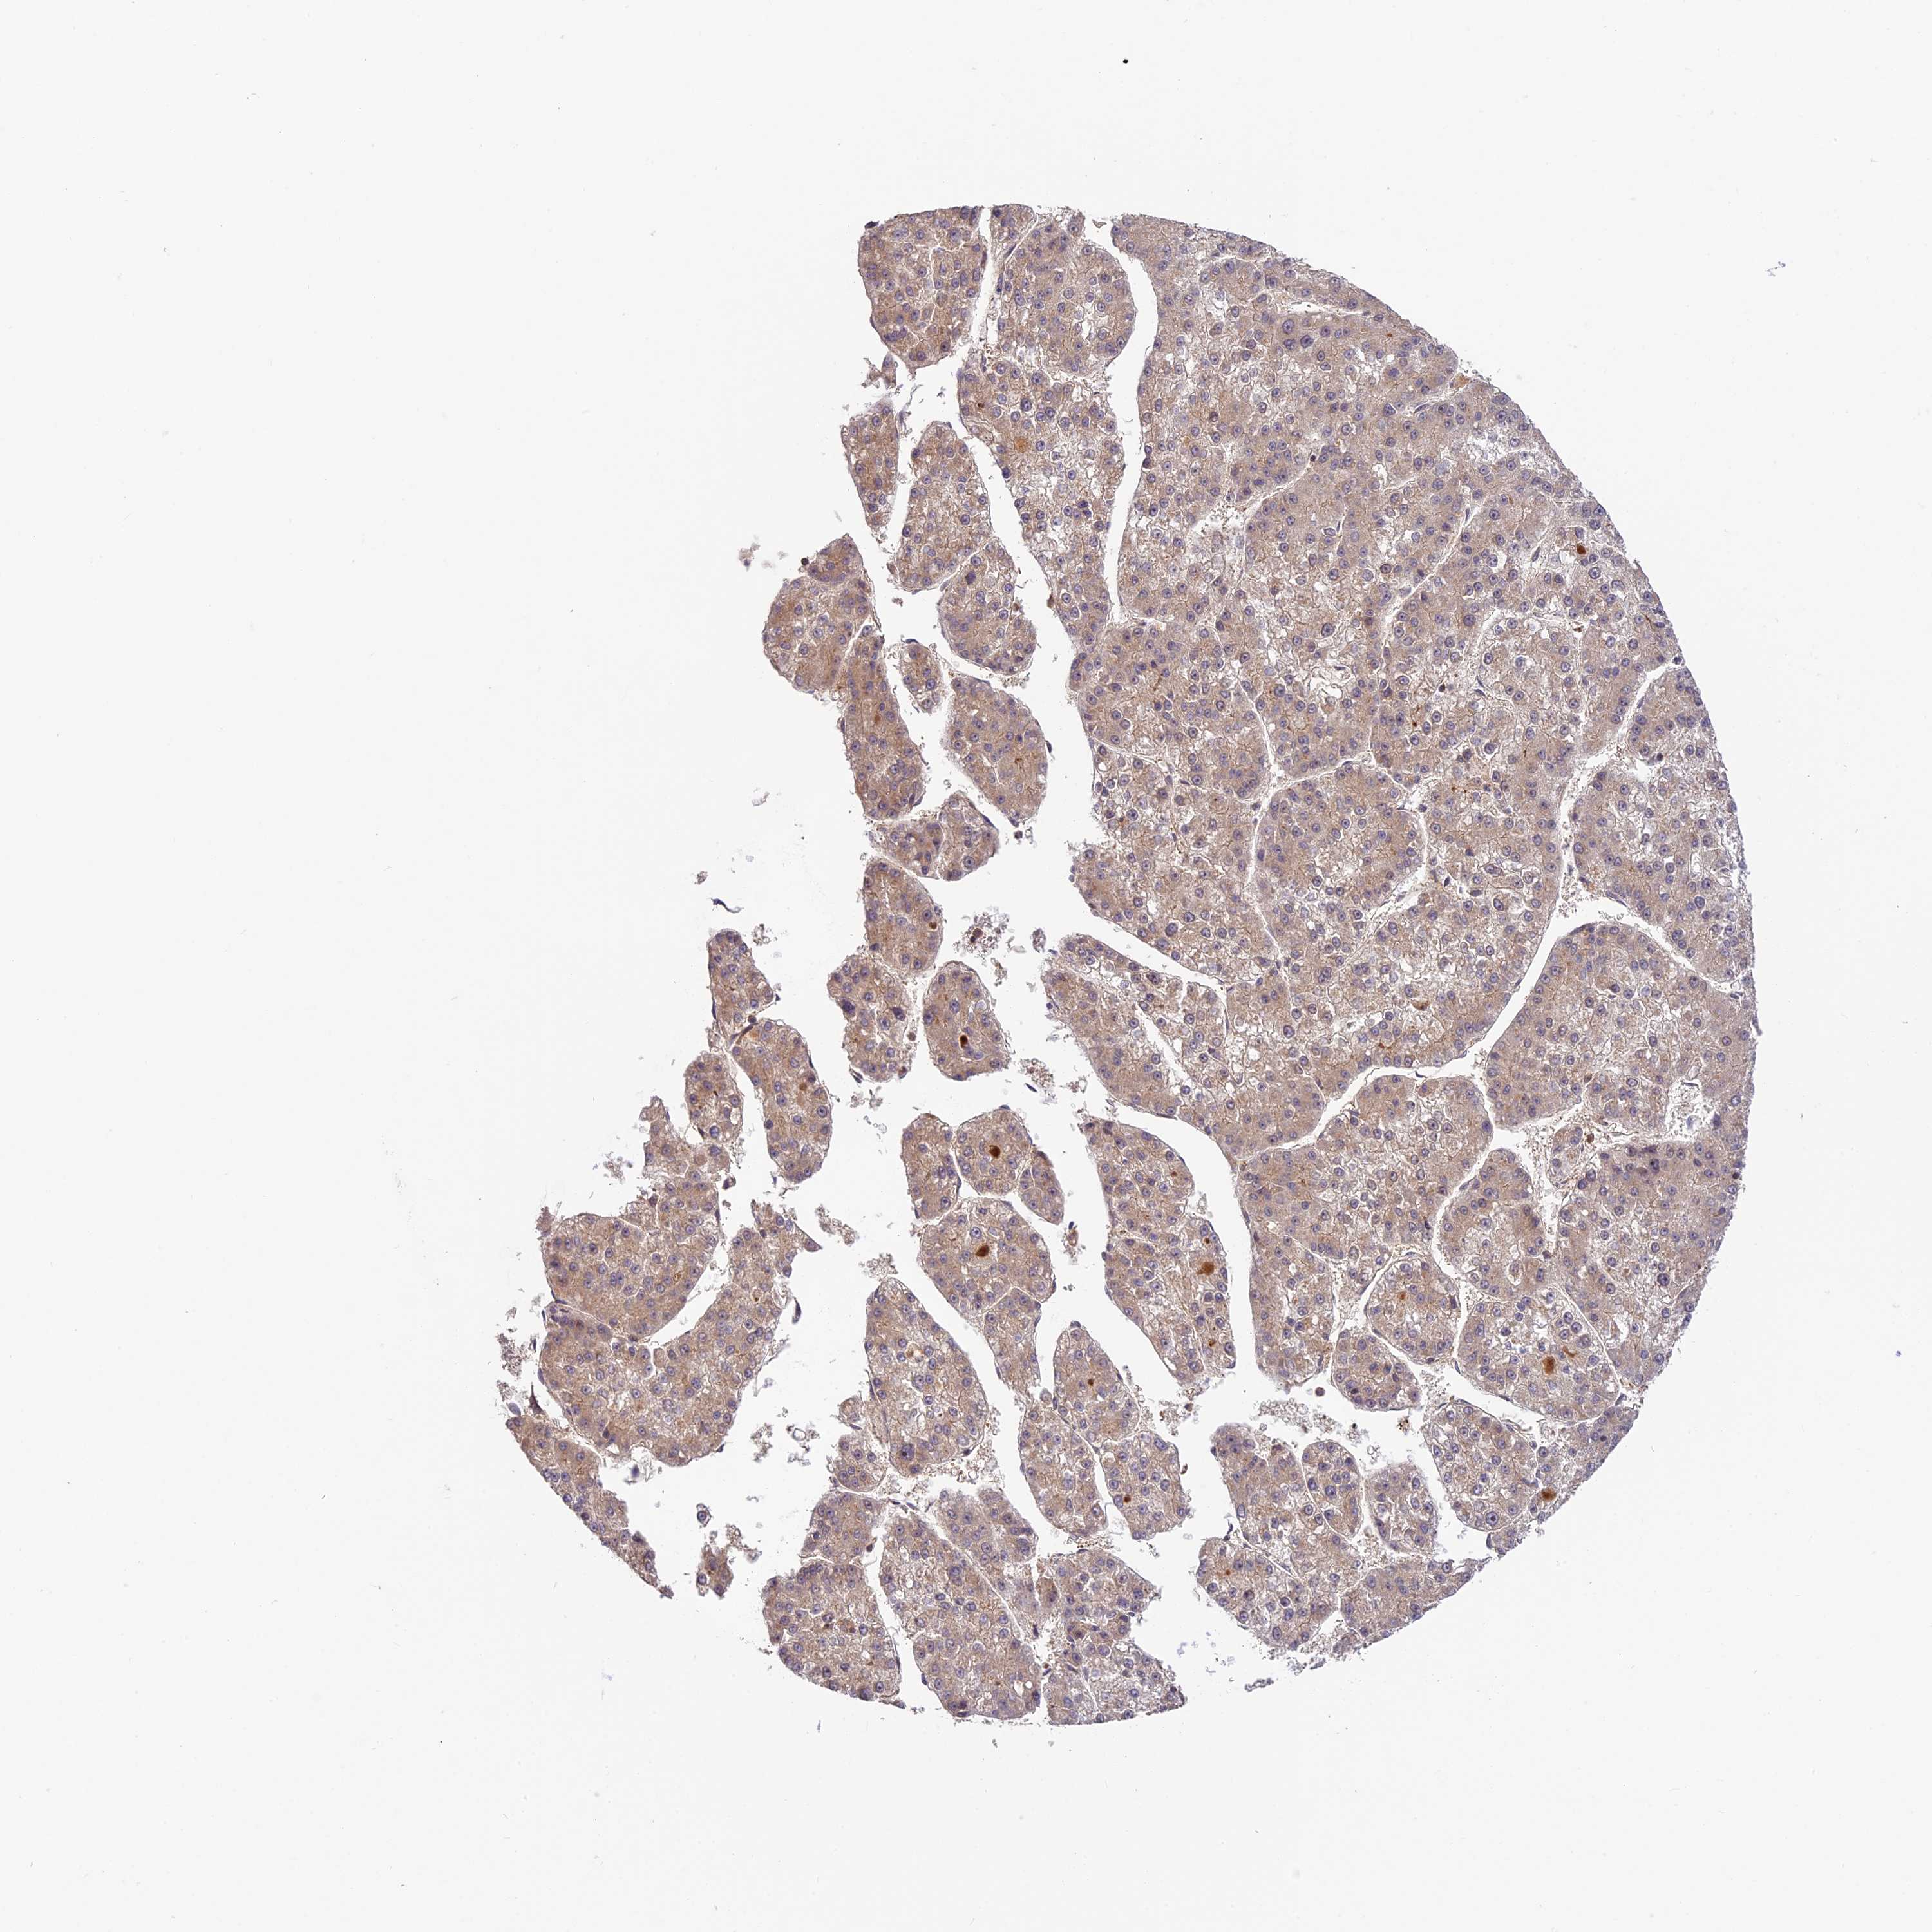

LIVER CANCER - Protein expressioni

A mouse-over function shows sample information and annotation data. Click on an image to view it in a full screen mode. Samples can be filtered based on level of antibody staining by selecting one or several of the following categories: high, medium, low and not detected. The assay and annotation is described here.

Note that samples used for immunohistochemistry by the Human Protein Atlas do not correspond to samples in the TCGA dataset.

Antibody stainingi

Antibody staining in the annotated cell types in the current human tissue is reported as not detected, low, medium, or high, based on conventional immunohistochemistry profiling in selected tissues. This score is based on the combination of the staining intensity and fraction of stained cells.

Each image is clickable and will lead to virtual microscopy that enables deeper exploration of all samples and also displays staining intensity scores, fraction scores and subcellular localization as well as patient and tissue information for each sample.

Antibody HPA039533

Antibody HPA040355

Staining

High

Medium

Low

Not detected

Intensity

Strong

Moderate

Weak

Negative

Quantity

>75%

75%-25%

<25%

None

Location

Nuclear

Cytoplasmic/membranous

Cytoplasmic/membranous,nuclear

Cholangiocarcinoma

Carcinoma, Hepatocellular, NOS